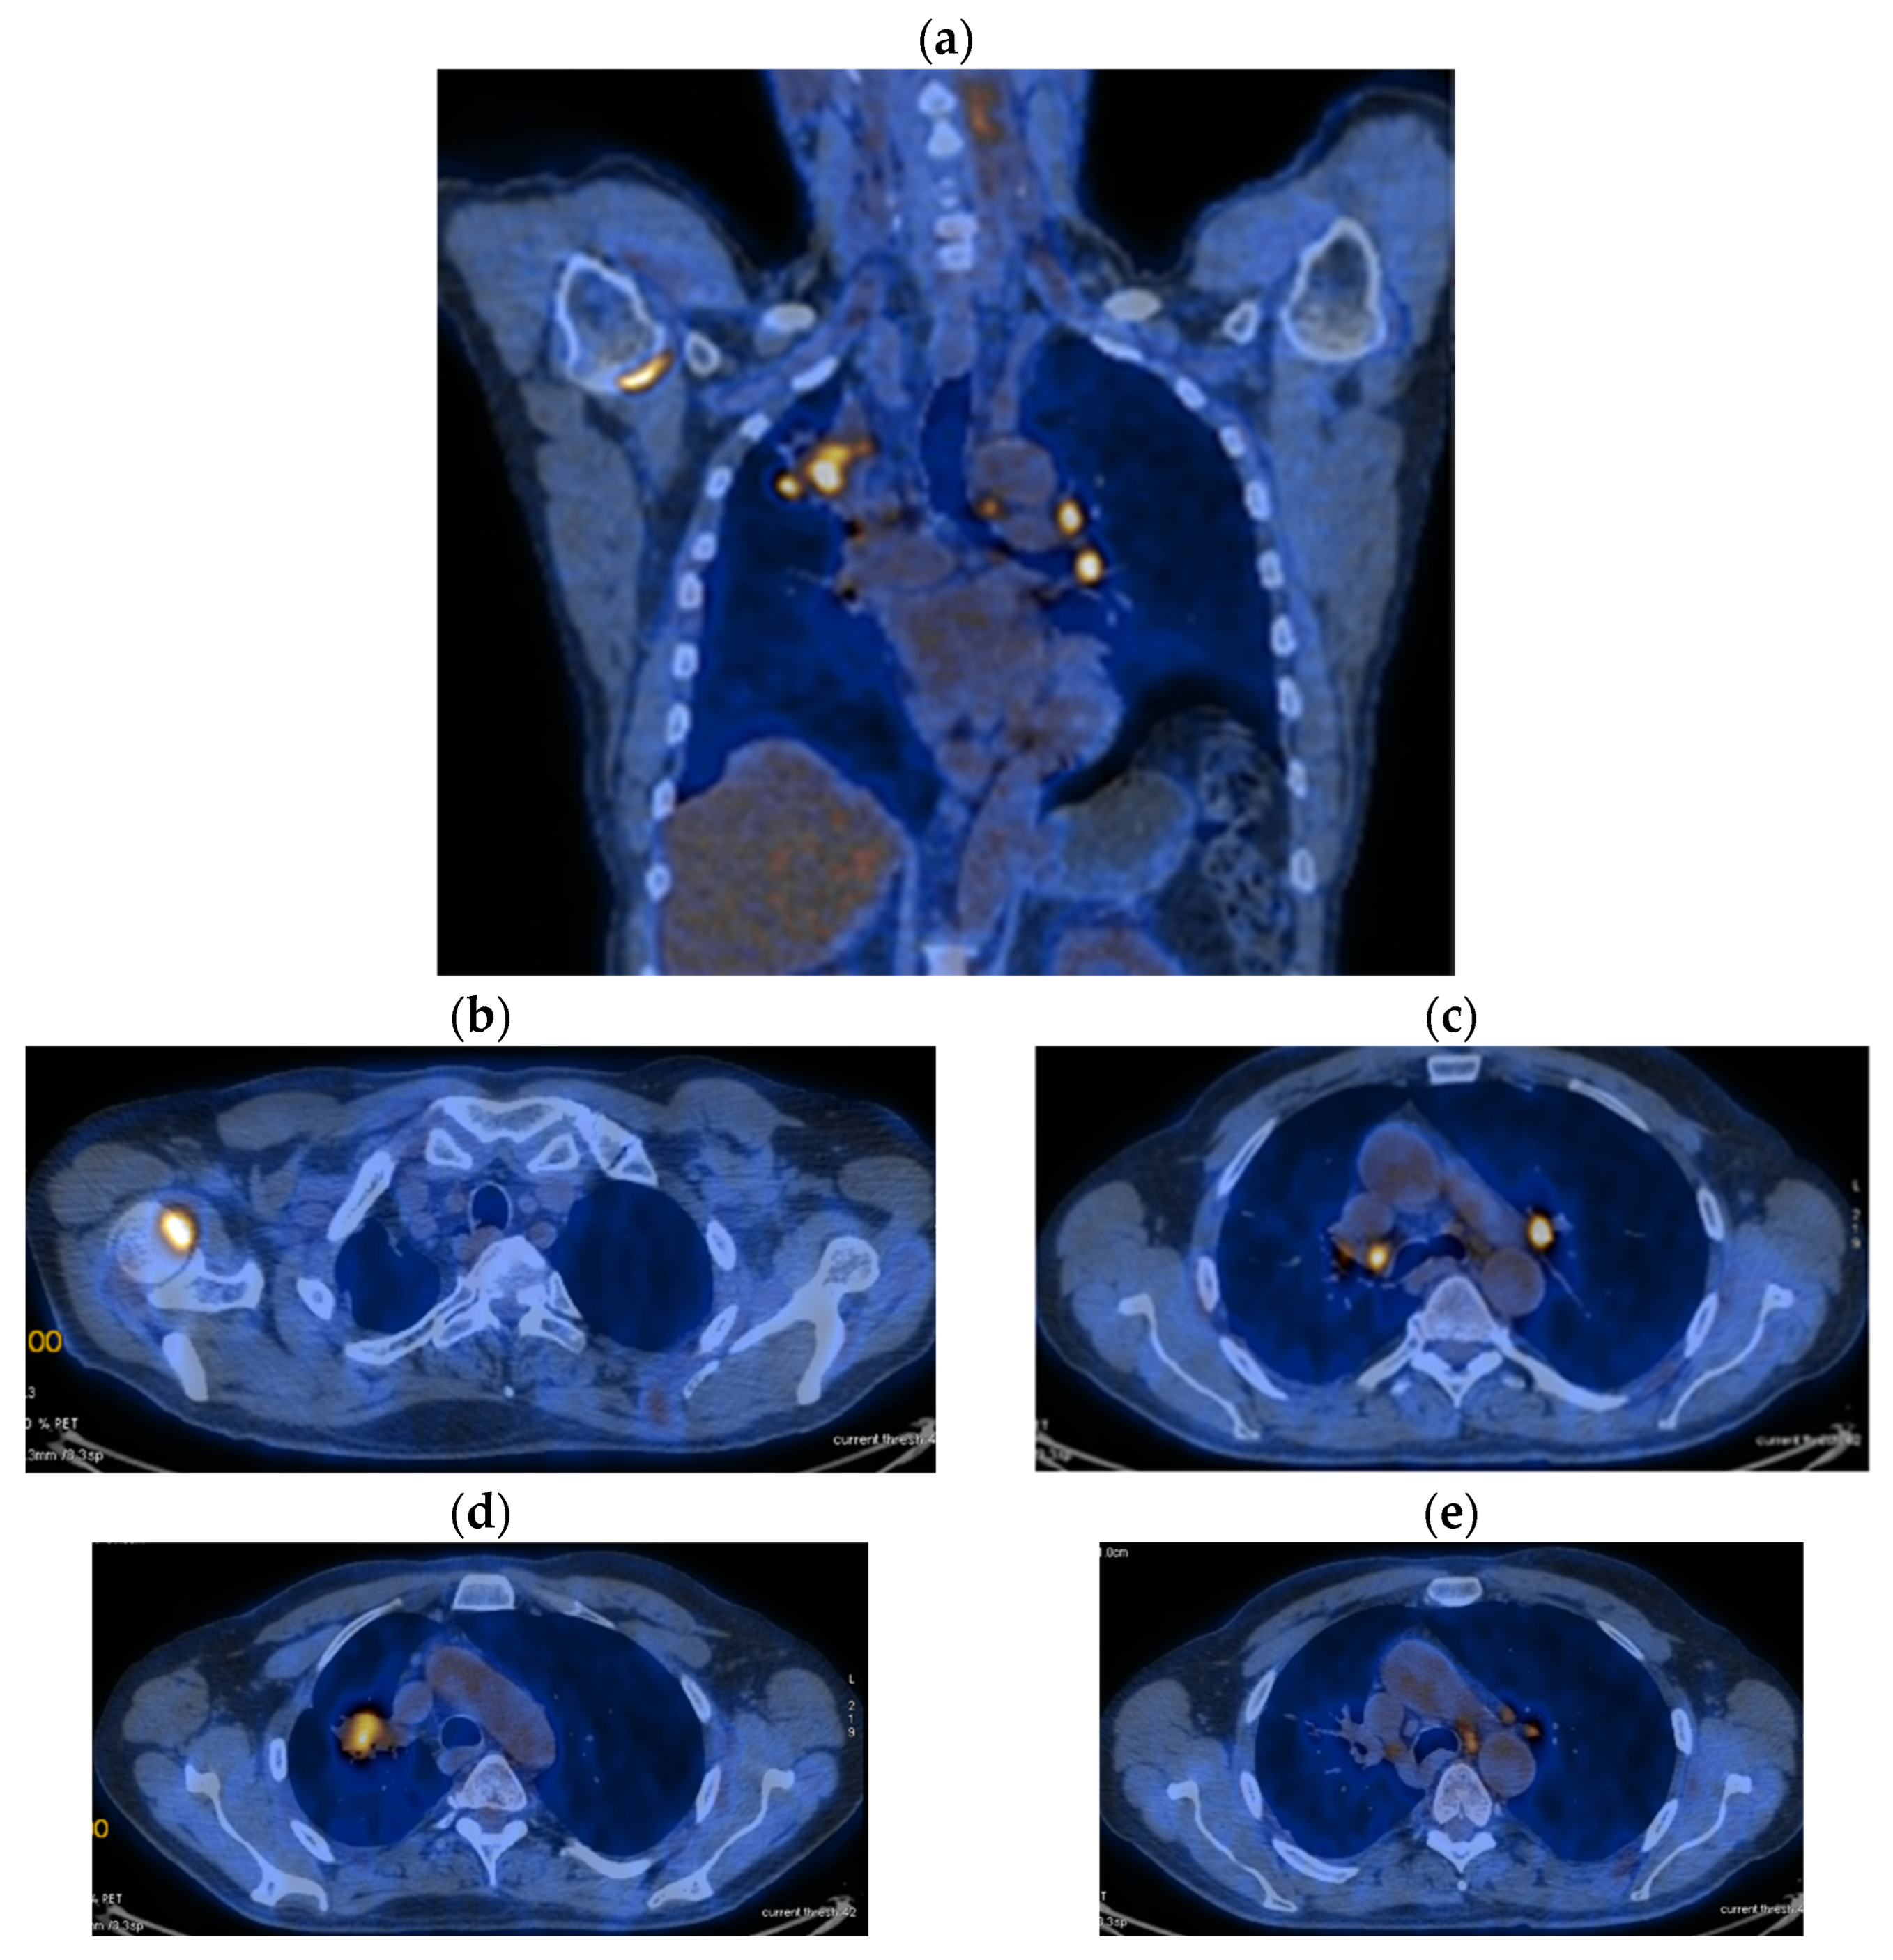

2. Case Presentation

2.2. Monitoring 2022: Oncological Commission 1910/16.08.2022

2.3. Oncological Committee 07/25/2023 Recommended

- Consider rescue re-irradiation (SBRT), taking into account the current primary tumor dimensions of 24 × 34.2 mm on PET CT from 06/2023 and also the total dose previously administered (08–09/2020), the previously applied fractionation, the time between the two irradiations, the cellular repair time and the dose constraints for the organs at risk.